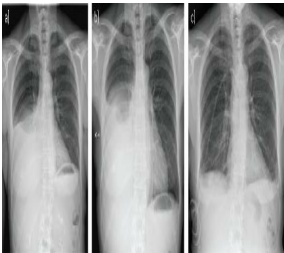

In this CXR -Is the ETT Placed correctly?

No ETT it is a RMB intubation

Case courtesy of Aditya Shetty, <a>Radiopaedia.org</a>. From the case <a>rID: 26991</a>